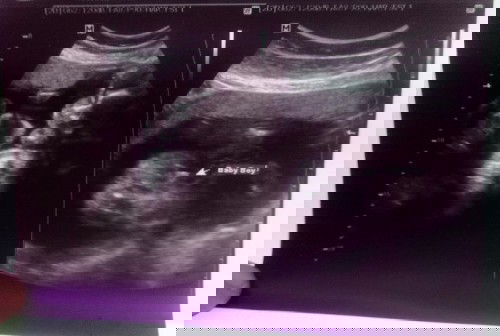

Baby boy or no?

Hello mga mi! ❤️ sure po ba na baby boy yung nasa ultrasound? may chance pa po kayang magbago? 5 months preggy here! 🥰 #advicepls #1stimemom #pregnancy

kitang kita po yung penis